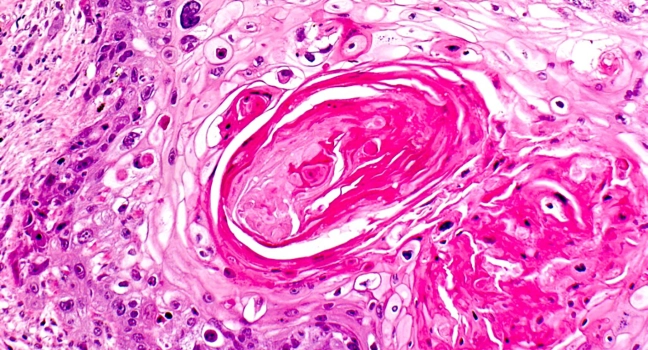

Iedere patiënt verdient de beste behandeling en die begint bij de juiste diagnose. Voor het stellen van de juiste diagnose is inzicht in de voorgeschiedenis van de patient van eerder cel- en weefselonderzoek een grote toegevoegde waarde. De data hiervan moeten veilig en gestructureerd worden opgeslagen en beschikbaar zijn voor de behandelende patholoog. Op deze manier kan de patholoog met volledige inzicht vanuit de pathologie, informatie bijdragen aan het behandelteam.